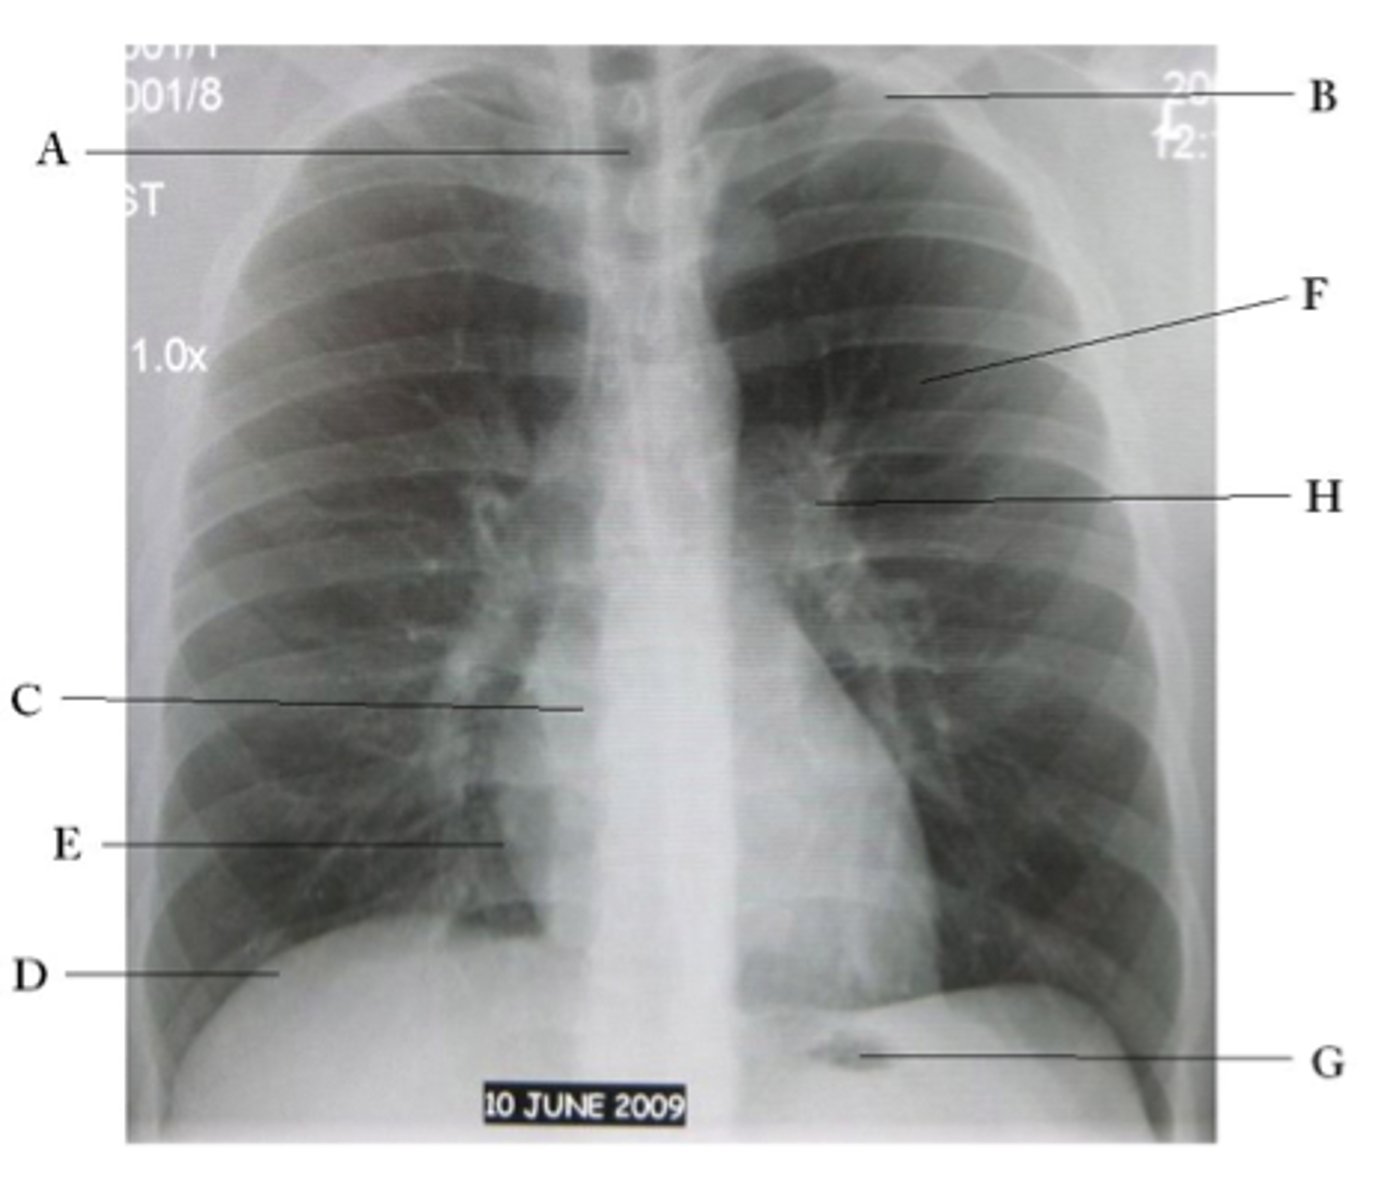

A

trachea

B

Clavicle

C

Right atrium

D

Diaphragm

E

Cardiophrenic angle

F

left upper lobe

G

gastric bubble

H

Left hilum